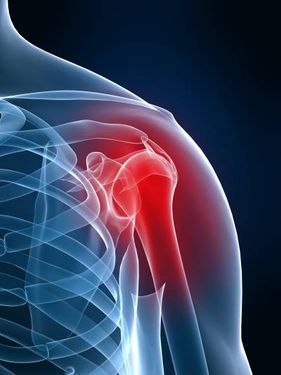

از تصاویر استوک در موارد زیادی می توان استفاده کرد، از جمله این موارد می توان طراحی بنر، طراحی پوستر، سایت، ویرایش عکس، چاپ تصاویر باکیفیت و... را نام برد.

عکس استوک کیفیت بالایی دارد، چون با دوربینهای حرفهای عکسبرداری میشود و از نظر موضوعات مختلف نیز تنوع بالایی دارد. رزولوشن تصاویر استوک معمولا بیشتر از ۳ تا ۴ هزار پیکسل است. به همین علت با ویرایش عکس در نرمافزارهای فتوشاپ و ایلوستریتور، از کیفیت عکس کاسته نمیشود. شما میتوانید با یک جستجوی ساده در سایت عرضه تصاویر استوک، به راحتی عکس موردنیاز خود را بیابید.